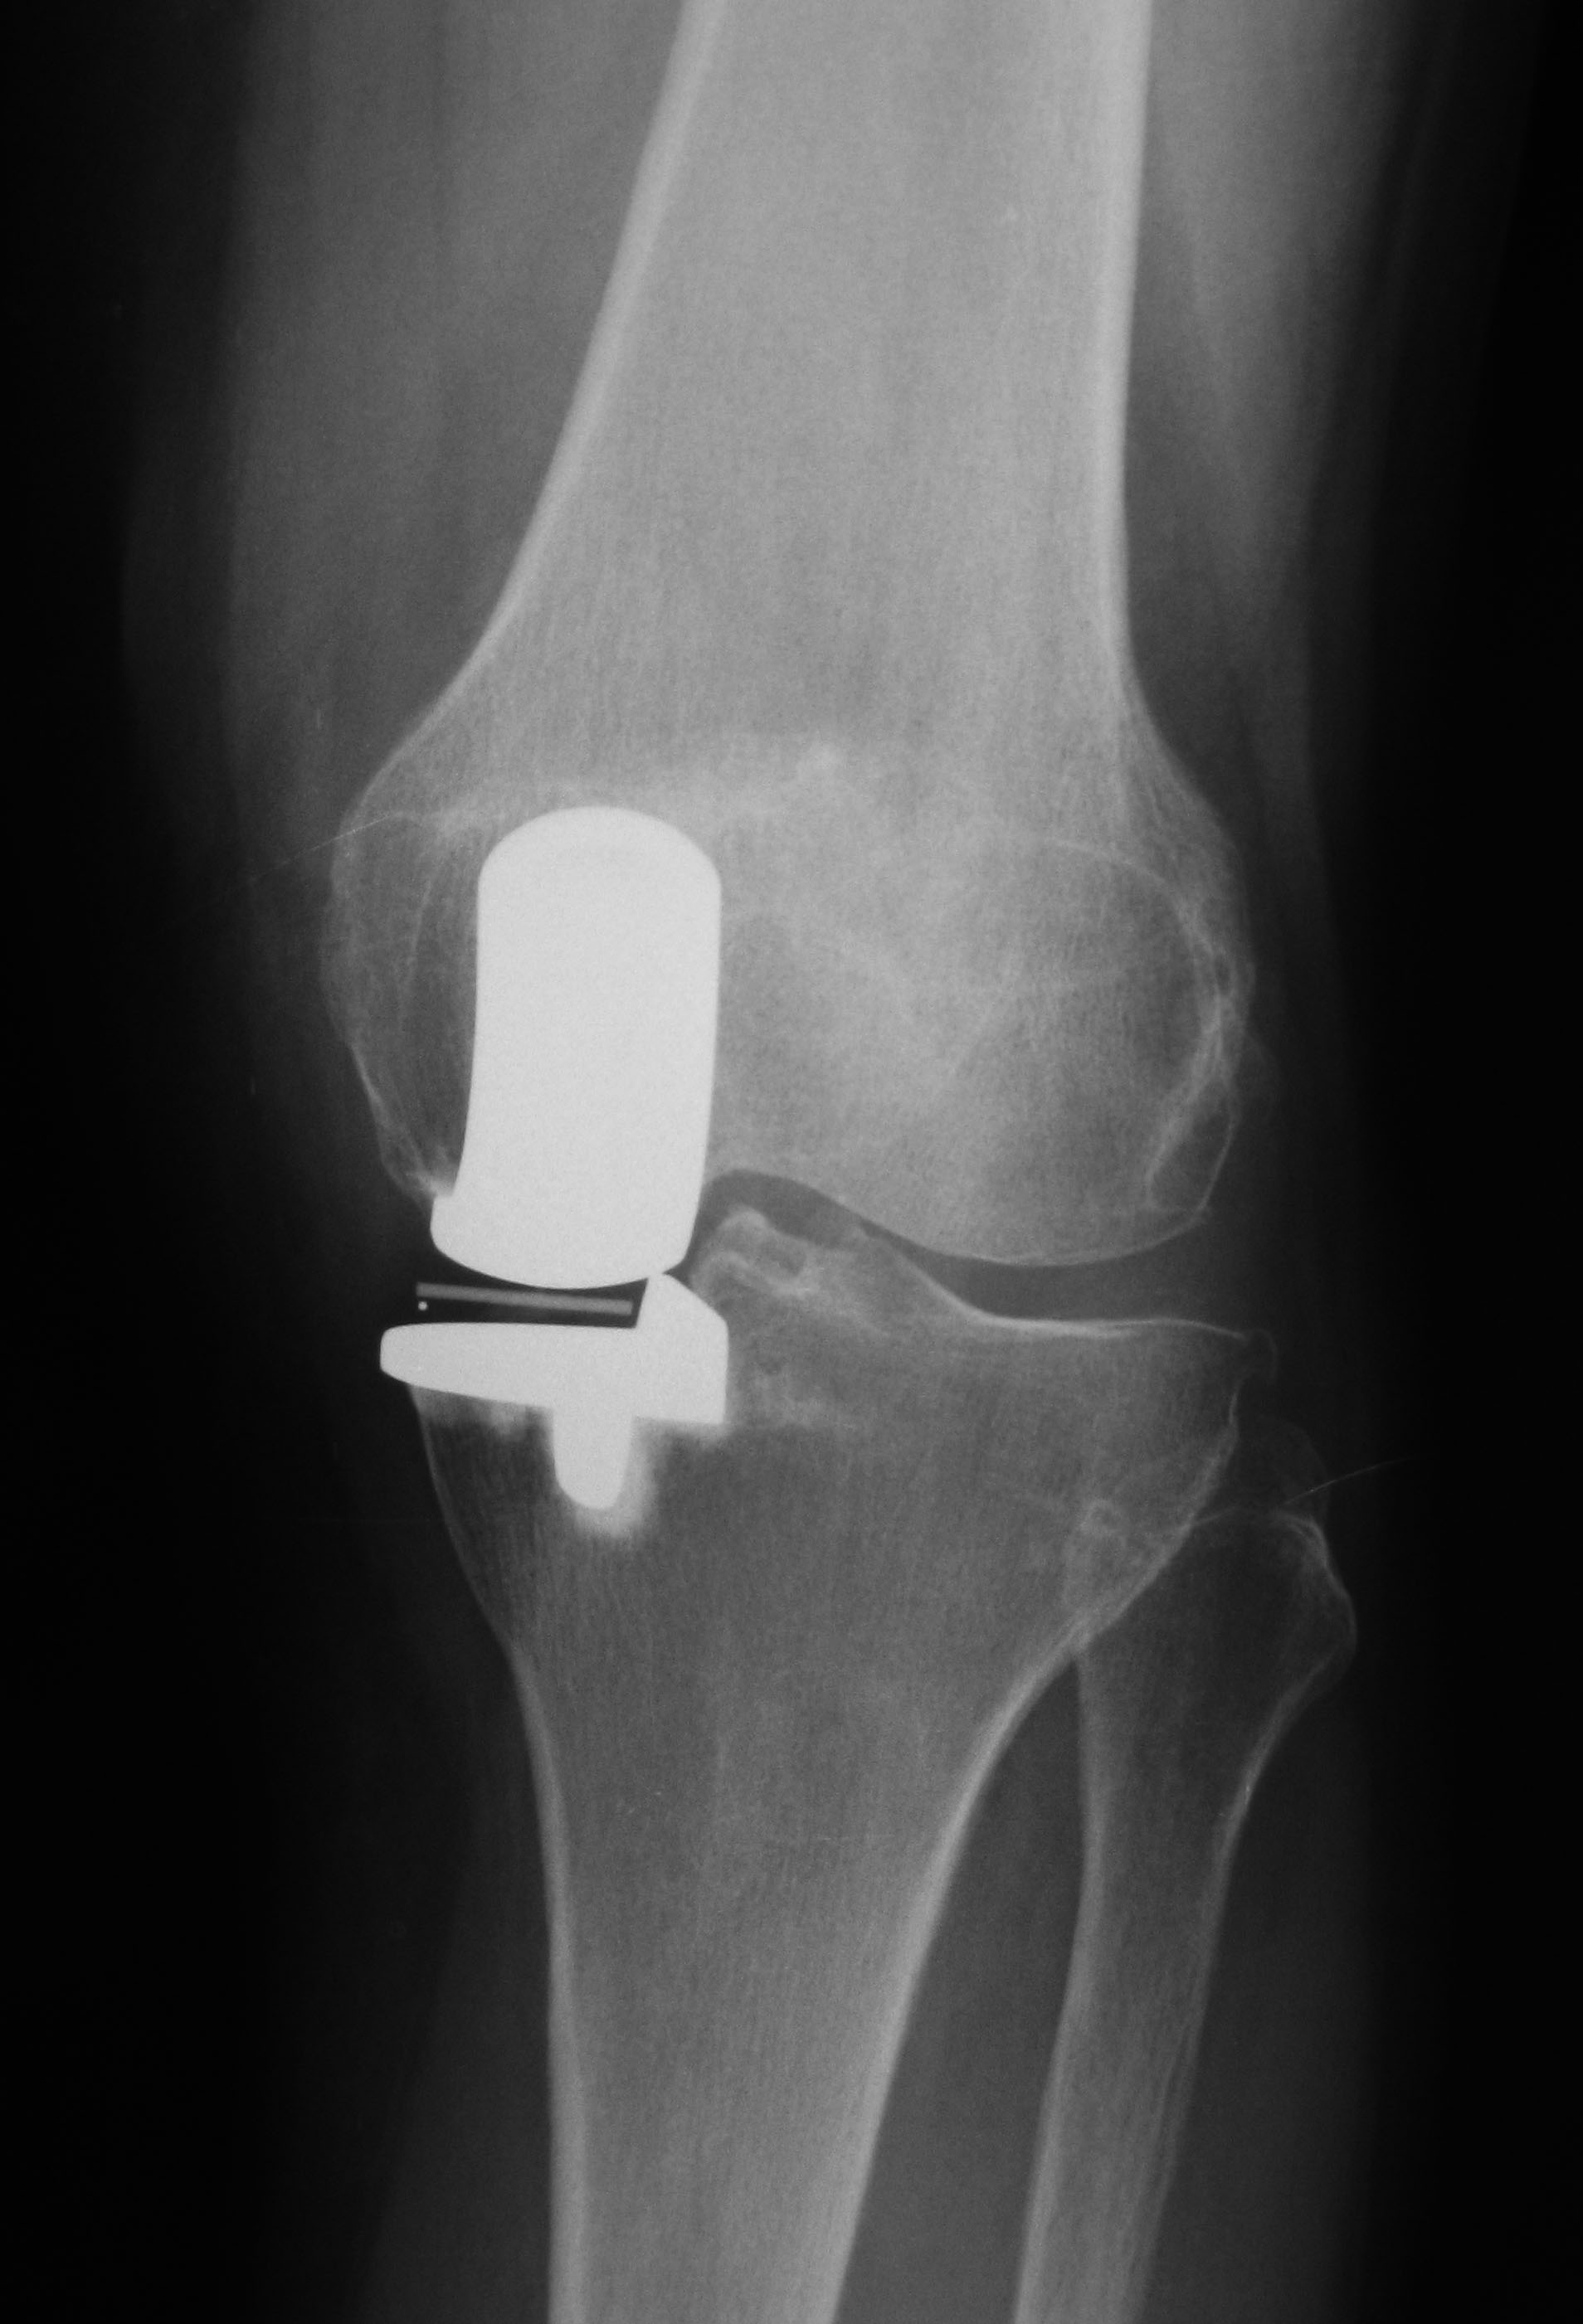

| 人工膝関節置換術(TKA) |

軟骨の変性が高度な患者さんや年齢が60歳以上の患者さんに行います。金属できた人工関節に置き換え、超高分子ポリエチレンの人工軟骨を挿入します。痛みはほぼ消失し、脚の変形の矯正も可能です。

(図2:TKA、正面)

(図3:TKA、側面)